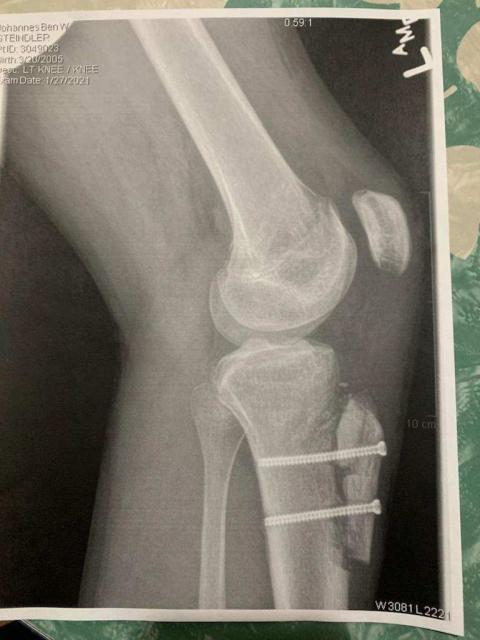

Don't show these to your wife...

[Linked Image]

He's better now though...